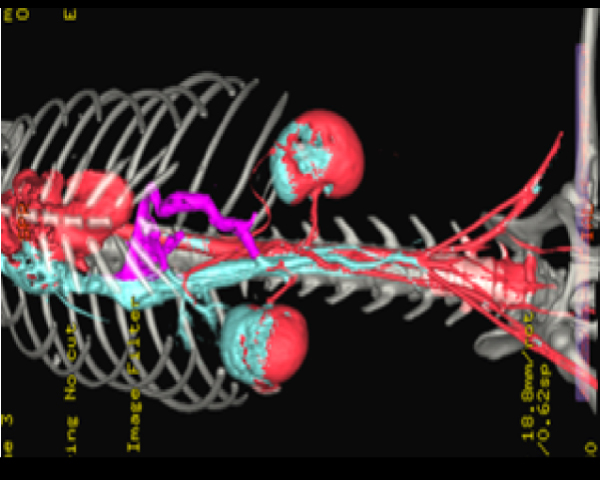

この症例の血管のCT画像